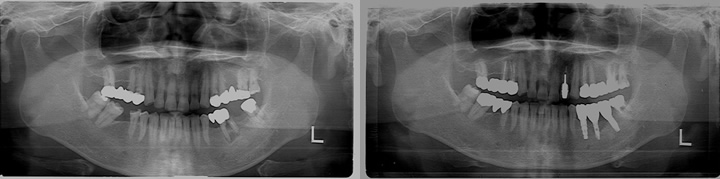

問診、口腔内検査、X線写真(2D)検査(下写真左・中央)、CT画像(3D)検査(下写真右)を行い総合的に診断を行います。

歯科治療では、インプラント治療に限らず見えない部位を診断するために上図のようなレントゲン写真を撮影する必要があります。

しかしながら、立体的な被写体(歯、顎骨など)に対してフィルムやパソコン上に写っているものはあくまで平面的な(2次元的な)像で実物とは異なります。

CT 撮影をすることによってインプラントを埋入する骨の状態(厚み、高さ、欠損状態、密度)や神経・血管の位置をあらかじめ正確に把握でき、安全に速いインプラント治療が可能となりました。